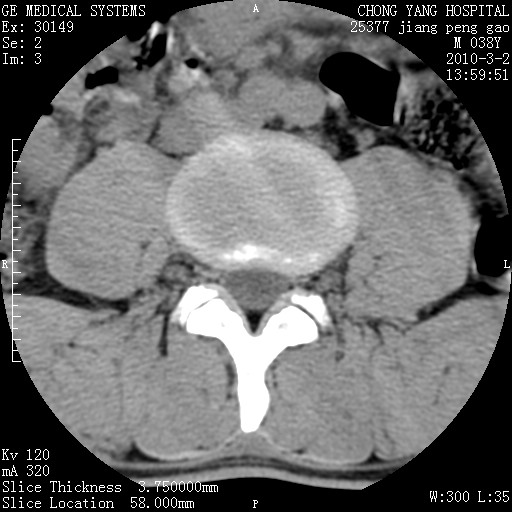

标题: CT24887:M38Y 反复腰痛 无外伤史 未做针灸 竖脊肌为何积气 [打印本页]

标题: CT24887:M38Y 反复腰痛 无外伤史 未做针灸 竖脊肌为何积气

退变,轻度增生/间盘膨出、l5椎后缘软骨结节。

肌间隙积气过多也为退变表现。

椎间盘突出,软组织积气。